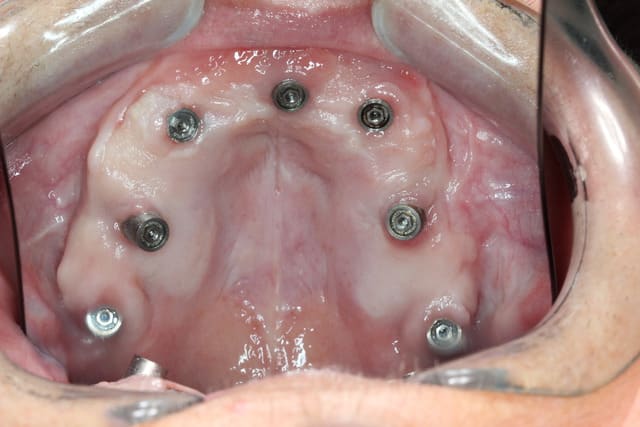

Seuls les 2 PLM 3.5 des plaques zygomatiques ont été ôtées pour le définitif... Celles des plaques pariétales et du monodisk était pil à ras de gencive tant cela a bien proliféré

G1 n exite plus même pas pour les disk car trop peu d espace laissé à os à base du disk ... C est un peu comme un switching plateform de passer de 4.5 mm au pilier à 2.35 au fût

G 0 n a jamais existé pour la raison décrite pour G1...

Néanmoins je n emploie plus les plaques G3 mais uniquement les G2 , ce qui est un grand progrès...

Mais j ai aussi eu des émergences pfs trop haute par rapport à l épaisseur muqueuse mais ça c était avant d employer du nanobone

Pp